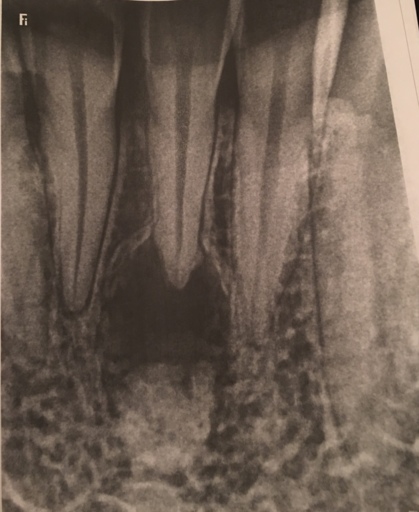

What can this be?

I went for a wisdom tooth removal but they found this space under tooth #24 after doing my X-ray examination.. I’m really scared that I might loose the tooth or have to have a tooth removed. I don’t have any pain with the tooth and no problems as to...